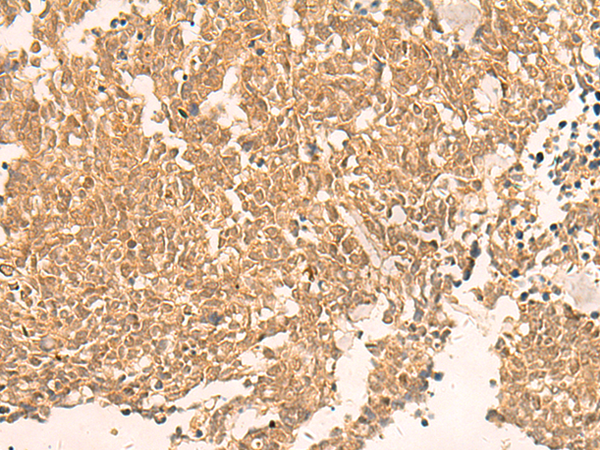

IHC positive control: |

Human ovarian cancer and Human lung cancer |

IHC Recommend dilution: |

40-200 |